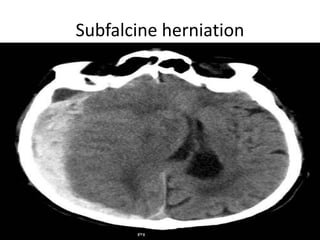

CNS herniations

• There are a number of different patterns of

cerebral herniation which describe the type of

herniation occurring:

• subfalcine herniation

• transalar herniation: ascending and descending

• transtentorial herniation

– downward: uncal herniation

– upward: ascending transtentorial herniation*

• tonsillar herniation*

• extracranial herniation

Subfalcine herniation